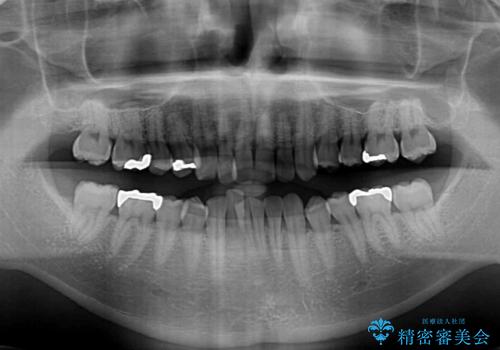

- 深い咬み合わせによる食いしばりで、顎関節や頭が痛むことがあるとのことで来院された患者様です。

歯ぎしりができないくらい強い食いしばりの咬合状態であったため、奥歯の歯軸を起き上がらせることで咬合を挙上させ、歯ぎしりができるようにしていくこととしました。

下顎が左側にずれているため、上下正中は最大限合わせられるところまで合わせるゴールとなりました。